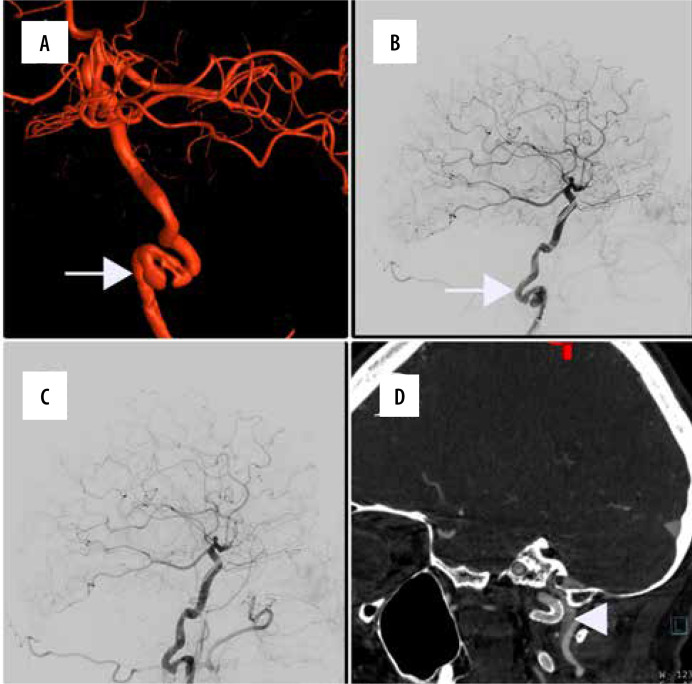

Purpose: Extracranial internal carotid artery dissections (EICAD) remain a relatively common cause of ischaemic events in young patients. Currently, there is no consensus on standardised use of endovascular therapy in the treatment of these patients, but available data suggest that conservative treatment is not sufficient in 15% of cases. The aim of our study was to evaluate if endovascular stent placement was safe and effective for the treatment of extracranial internal carotid artery dissection, and whether it should be considered in properly selected patients.

Material and methods: This single-centre, retrospective study aimed to evaluate procedural and clinical outcomes of patients with EICAD who underwent endovascular stenting between 2015 and 2024. Procedural and clinical efficacy and safety, the rate of complications, and long-term outcomes were noted.

Results: A total of 21 patients (10 females) with an average age of 53 years underwent stenting for EICAD. Technical success was achieved in all cases. Perioperative complications were noted in 2 cases. Neurological evaluation performed at 6-month follow-up showed very good clinical results in the majority of cases (mRS 0 and mRS 1 were 76% and 19%, respectively). Control imaging examinations confirmed stent patency in all cases. No long-term mortality was observed.

Conclusions: This retrospective study demonstrated procedural and clinical safety and efficacy of endovascular stenting in patients with extracranial internal carotid artery dissection. That is why endovascular therapy should be proposed to individuals with unsatisfactory response to medical treatment and in cases of disease progression.